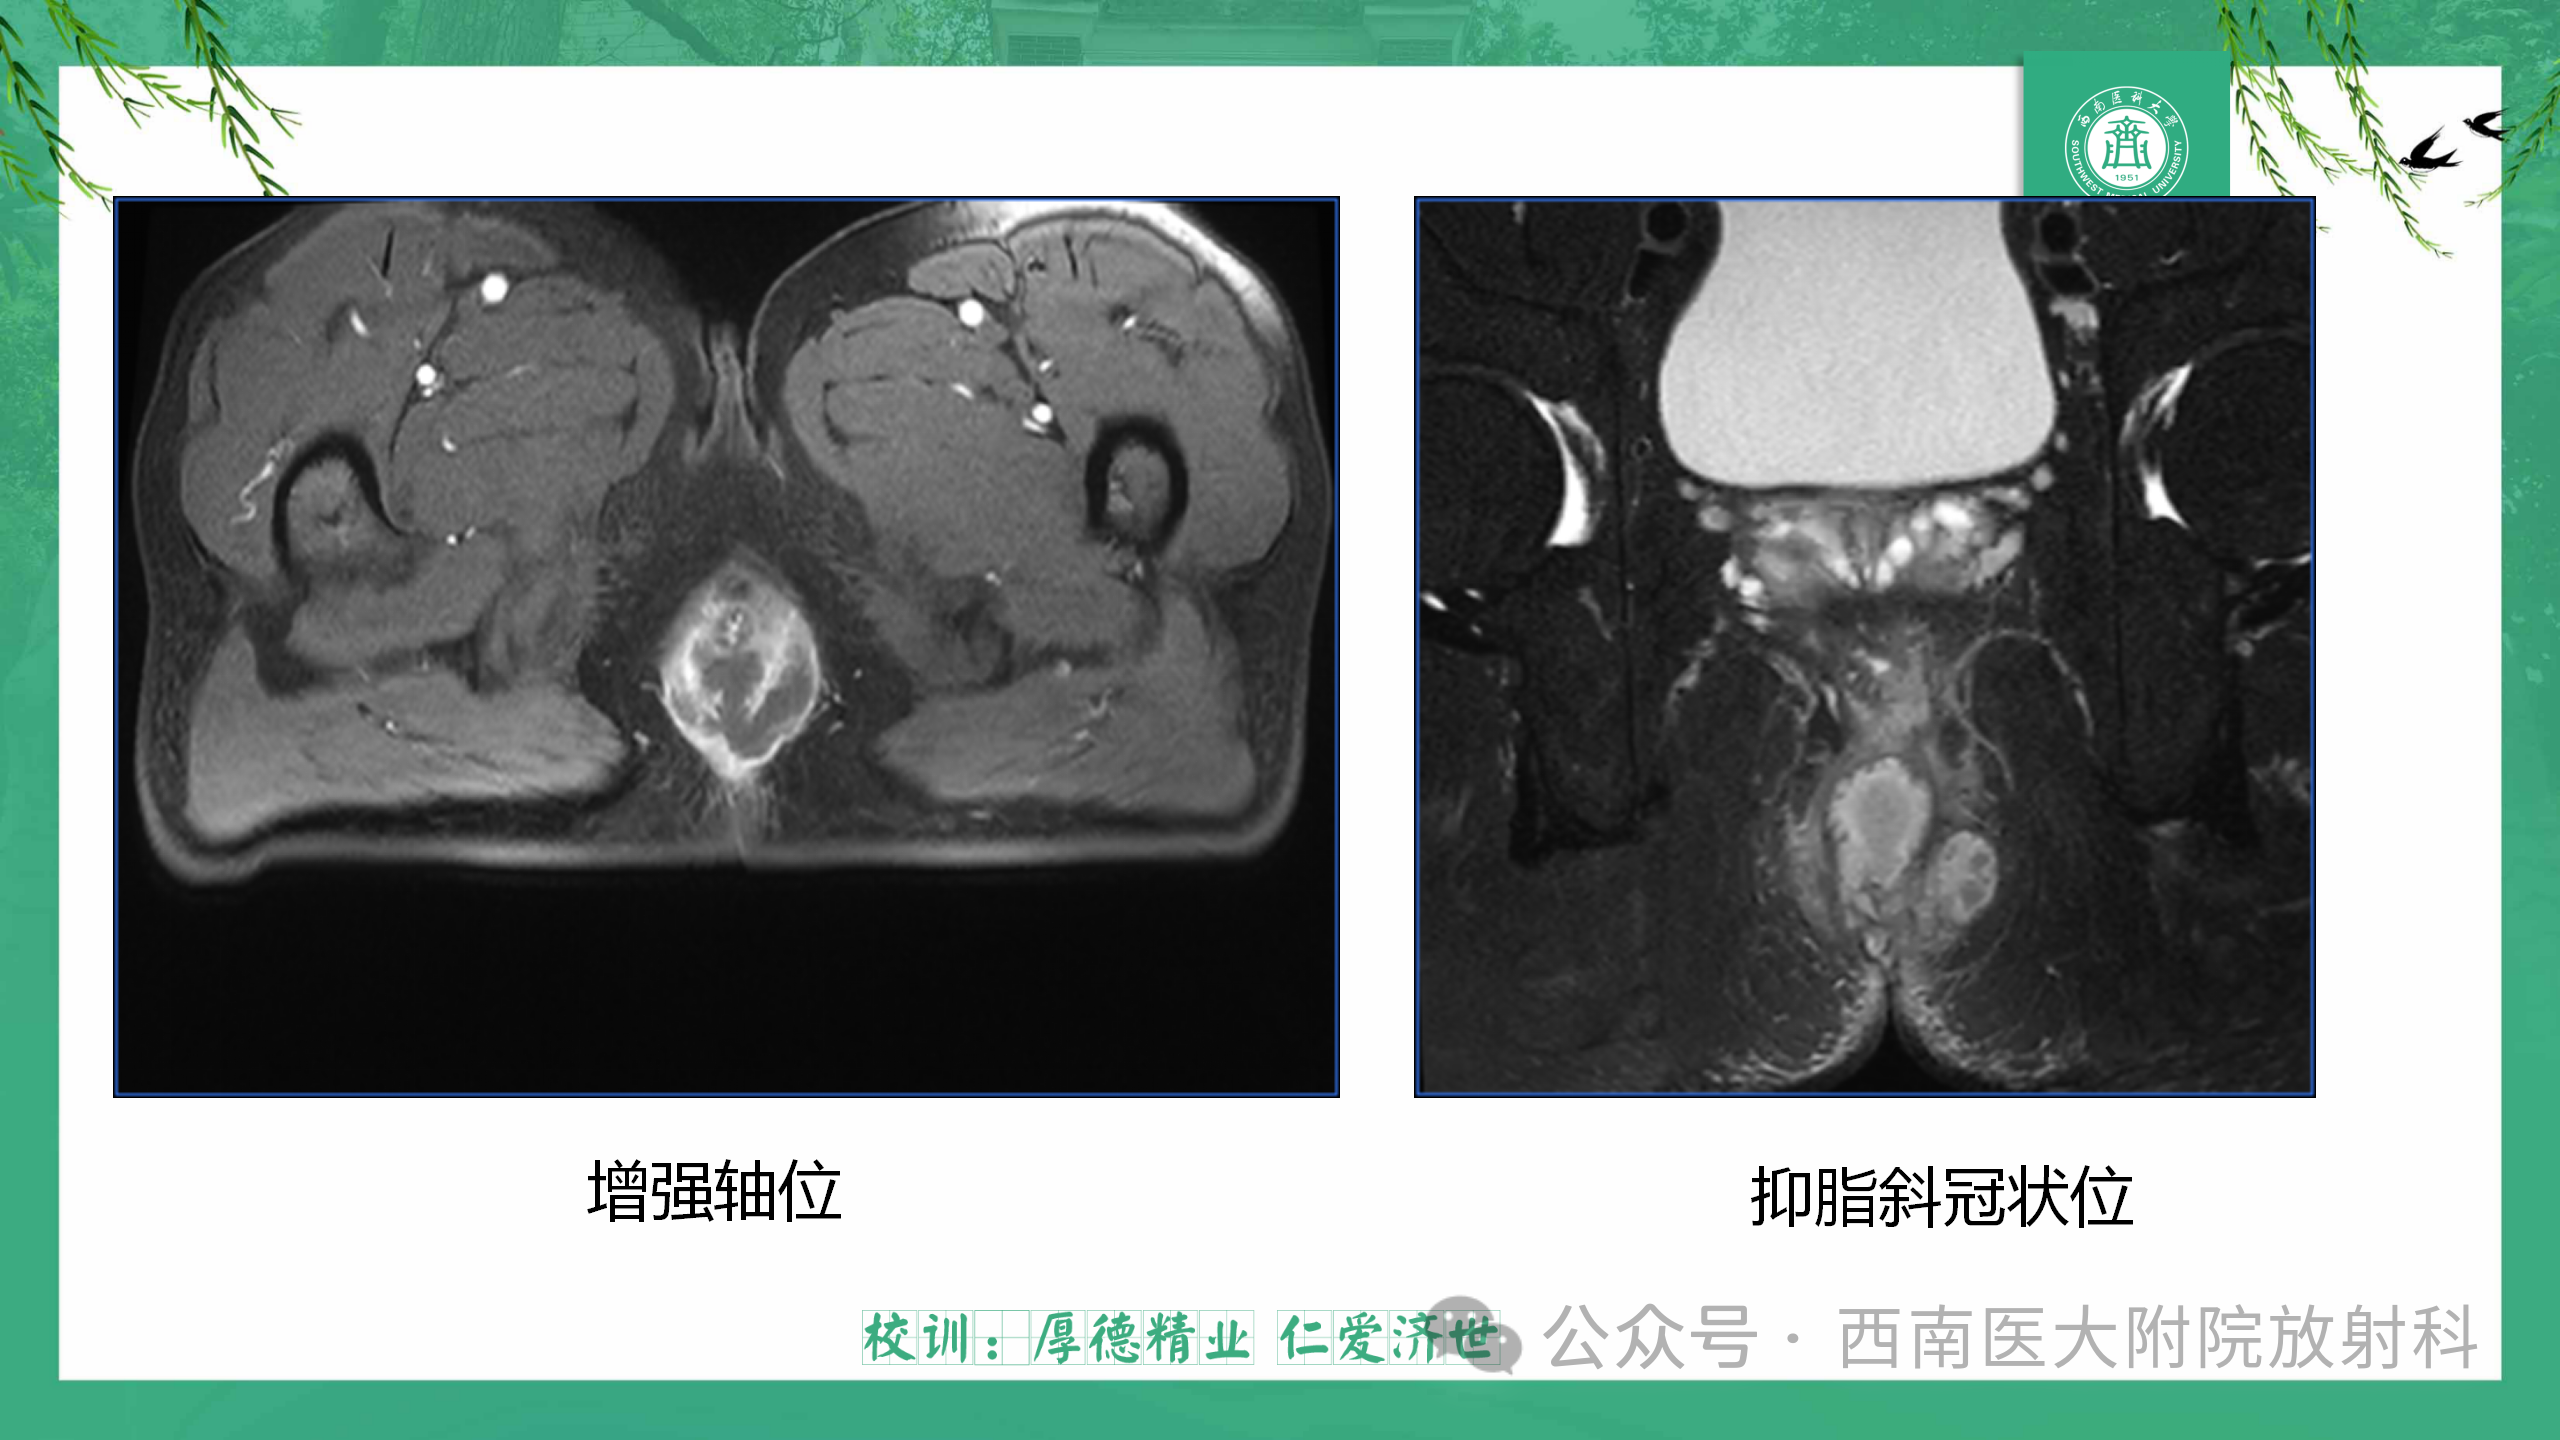

肛瘘的MRI表现